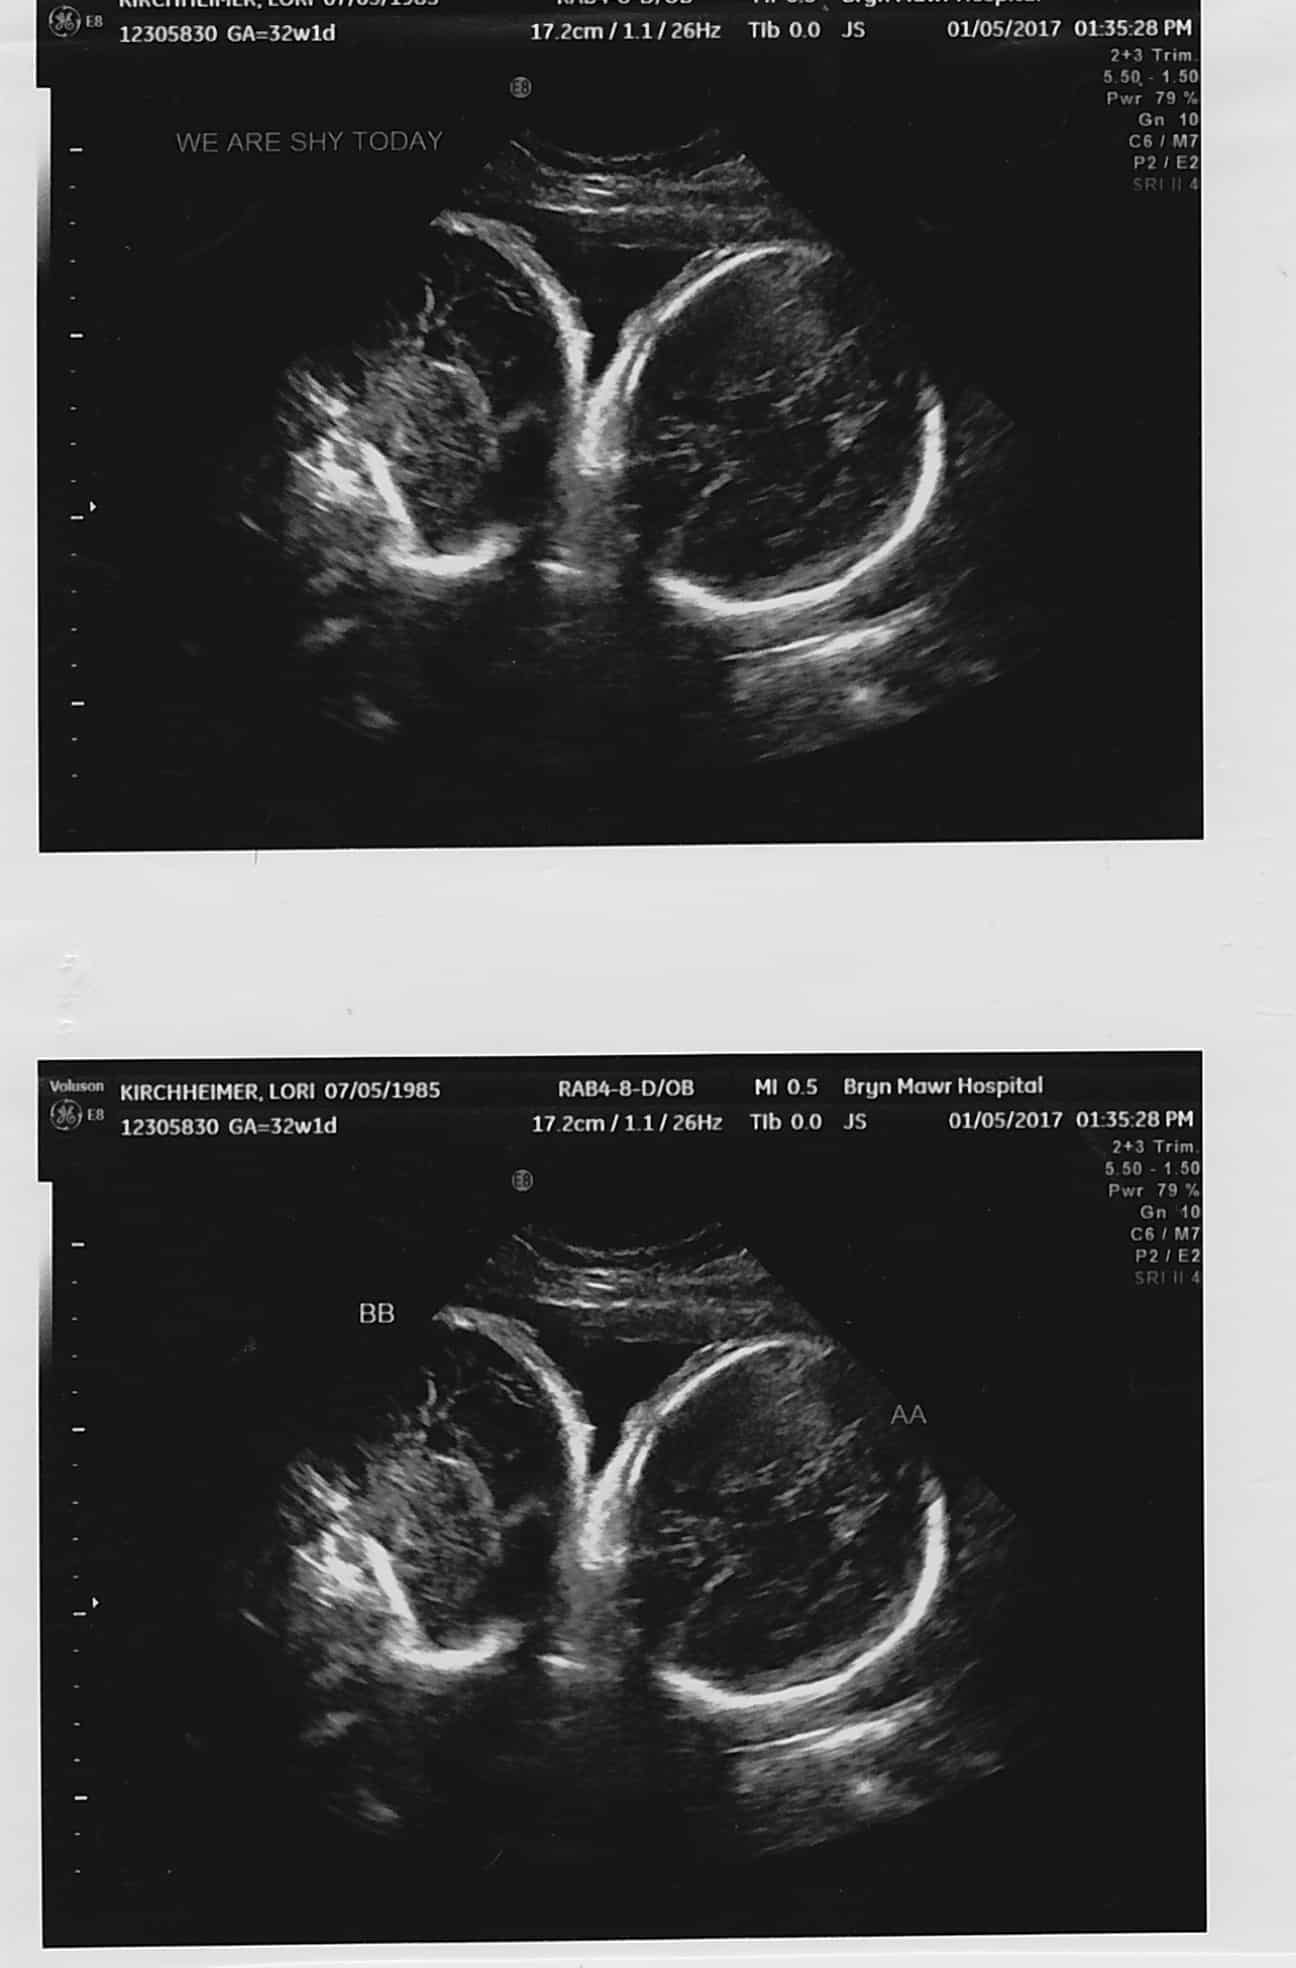

- Ultrasound Photos at 32 Weeks Pregnant With Twins

Ultrasound Photos at 32 Weeks Pregnant With Twins